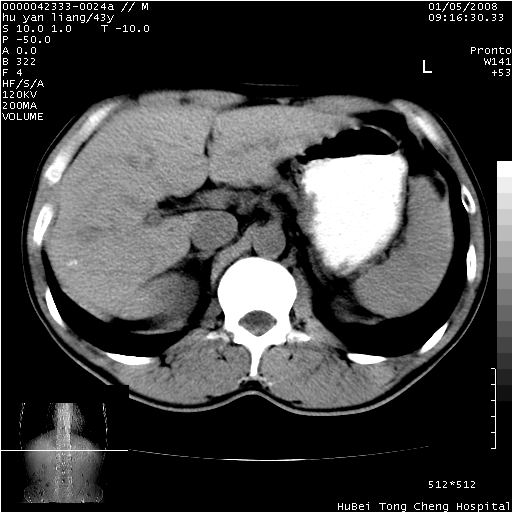

患者 男,43岁。右上腹不适1年余。既往有“肝右叶肝脓肿”病史,经保守治疗后痊愈。

b超提示:1)肝右叶肝内胆管结石。2)肝右叶占位性病变待排。

上中腹部ct轴位平扫+增强扫描(层厚10mm,螺距1.0,重建间隔10mm),图像如下:

肝右上叶偏后方较大团片状钙化灶,支持:肝脓肿后遗改变!

肝右叶后段团块状钙化灶,结合病史考虑肝脓肿痊愈后表现。